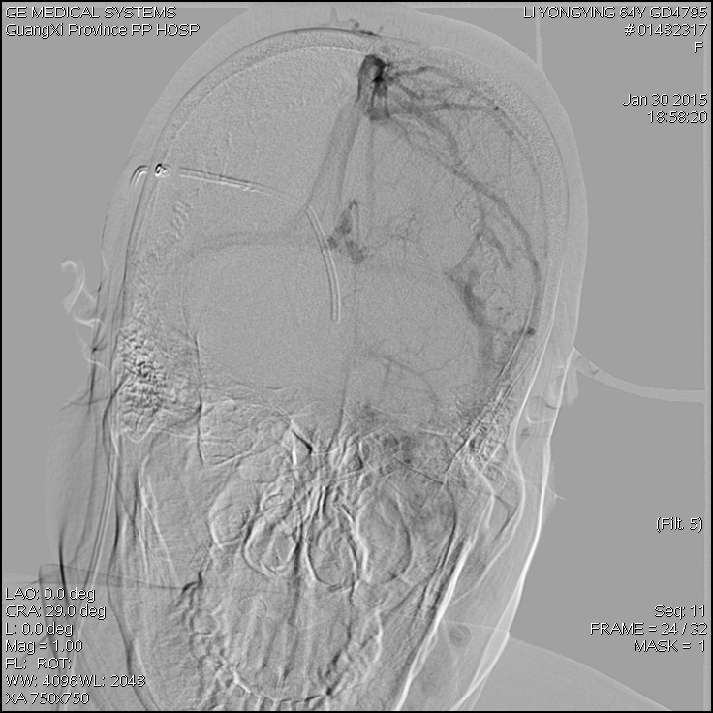

2015-1-30 DSA

脑压为60mm水柱

2015-2-1

在局麻下行腰椎穿刺术+ 测脑压术,患者取左侧卧位,测量脑脊液压力为60mm水柱。

再次呕吐3天;面部头痛有所缓解(卡马西平)。

调压200